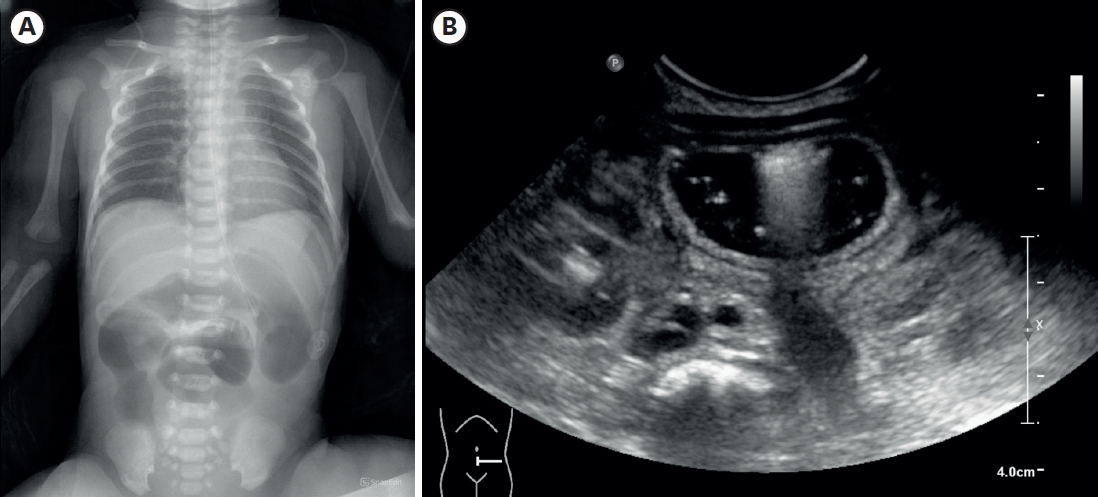

Intrapulmonary Bronchogenic Cyst in an Infant: Rare Presentation and Insights From Literature

Ramyasree Bade, Shailesh Solanki, Shivani Dogra, Nitin James Peters, Jai Kumar Mahajan

Adv Pediatr Surg 2025;31(2):87-92.   Published online December 24, 2025

DOI: https://doi.org/10.13029/aps.2025.31.2.87

Intrapulmonary bronchogenic cysts are rare congenital anomalies that often present diagnostic and management challenges due to nonspecific symptoms. We report a one-year-old female with progressive respiratory distress who was initially misdiagnosed with pneumothorax. Imaging revealed a large intrapulmonary cyst, and surgical excision confirmed the diagnosis. Early intervention ensured a favorable outcome, with no recurrence in one year. This case highlights the importance of considering bronchogenic cysts in pediatric respiratory distress and emphasizes the value of timely surgical management.